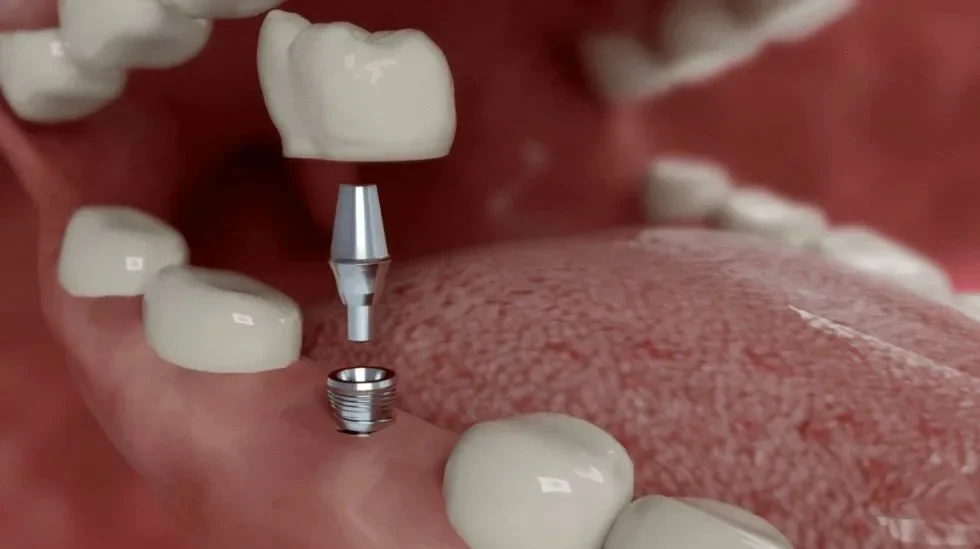

Solución duradera y estable para reemplazar uno o varios dientes mediante coronas o puentes cementados sobre dientes naturales o implantes.

En Mompell & Micó diseñamos soluciones protésicas que se adaptan a cada paciente. En muchos casos, el tratamiento con prótesis puede complementarse con técnicas avanzadas como la implantoprótesis (prótesis sobre implantes) o la combinación de prótesis fijas y removibles, según la cantidad de dientes a reemplazar y la calidad del hueso disponible. Este enfoque personalizado garantiza que cada prótesis sea cómoda, funcional y estéticamente natural, permitiendo recuperar la capacidad masticatoria y la armonía de la sonrisa. Además, planificamos cada paso del tratamiento para asegurar una integración perfecta y resultados duraderos que mejoran la confianza y la salud bucal del paciente.

Las prótesis sobre implantes ofrecen mayor estabilidad, comodidad y preservación ósea. Sin embargo, la elección depende de cada paciente, la cantidad de dientes a reemplazar y las condiciones óseas.